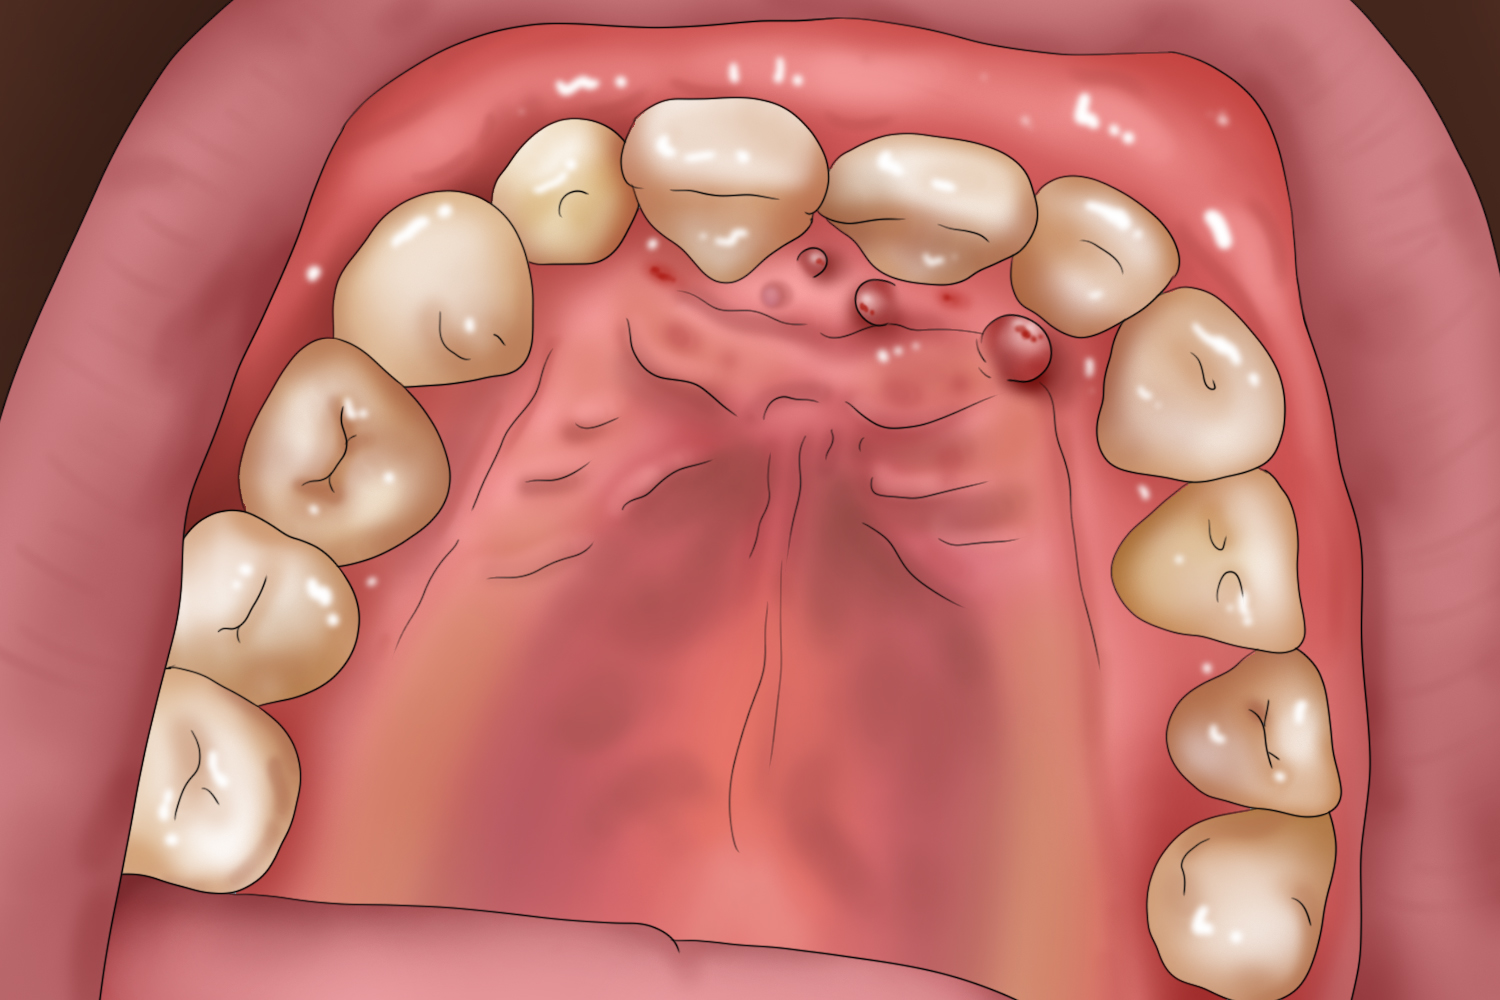

根尖肉芽肿

上牙若在慢性炎症刺激下有根尖肉芽肿形成,也可能出现口腔上颚长肉芽症状,表现为上颚靠近上牙根部处,有微微隆起的圆形肿物,部分患者伴有咀嚼不适、牙冠变色、牙龈脓包、叩痛等症状。